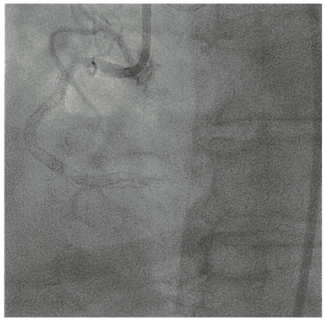

Technical Review

Richard Casazza, MAS, RT(R)(CI)

Even though crossing aortic valves isn’t a lost art, crossing may be more difficult for novice operators because of a lack of everyday practice in the cath lab.

Case Report

Adam T. Stys, MD, FACC; Tomasz P. Stys, MD, FACC, FSCAI; Filip Oleszak; Andrii Maryniak, MD

The authors present a case of guidewire fracture during angioplasty of a right coronary artery chronic total occlusion due to instent restenosis.